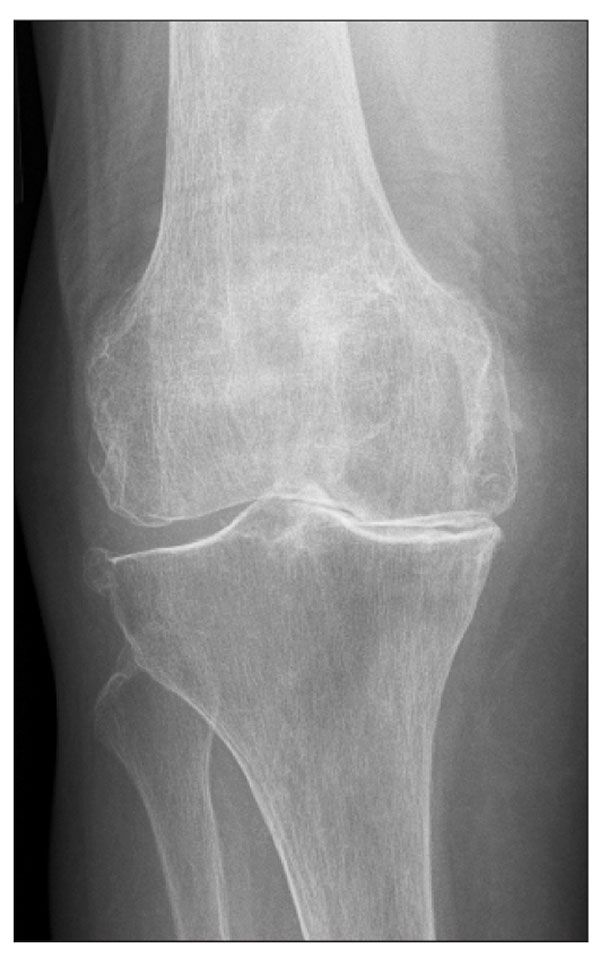

Question 2:

An 81-year-old man presented with a 1-year history of pain in his right knee. The pain had become more severe over the previous 2 months, but he denied any acute trauma or injury. The knee had limited range of motion. This anteroposterior x-ray view shows severe degenerative changes. The diagnosis was degenerative joint disease.